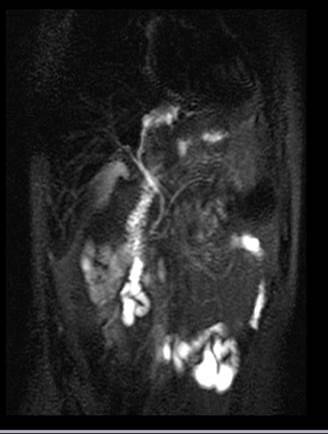

Se decide realizar ColangioRMN, que informa en proyección de lóbulo hepático izquierdo, segmento III, formación quística ovoidea, hipointensa en T1, hiperintensa en T2, de 20 mm x 25 mm, que provoca obstrucción en sistema biliar intrahepático izquierdo con dilatación. Vesícula sin imágenes endoluminales. Páncreas con aumento de espesor y colecciones peripancreáticas. (Fig. 1,2)

Fig. 1 y 2: RMN:Vía biliar intrahepatica derecha normal. En proyección de lóbulo hepático izquierdo, segmento III, se visualiza una formación quística ovoidea, hipointensa en T1, hiperintensa en T2, de 20 mm x 25 mm, que provoca obstrucción en sistema biliar Intrahepatico izquierdo con dilatación. ¿Quiste biliar congénito?